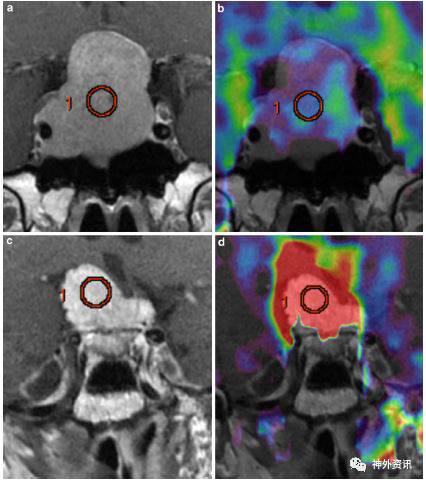

图3. 小脑桥脑角神经鞘瘤和脑膜瘤特征。注:MRI-T1加权轴向脂肪抑制成像对比:a、c图显示两个桥小脑桥脑角增强肿瘤。CBF图显示:b为非富血流灌注的神经鞘瘤(nTBF=0.85);d为富血流灌注的脑膜瘤(nTBF=3.29)。